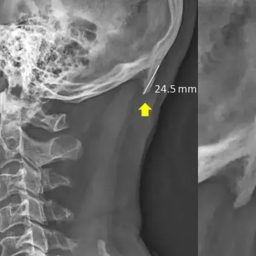

Рентген показал, что происходит с шеей зумеров из-за постоянного скроллинга соцсетей. «Рога из черепа»

Ученые продолжают говорить о вреде смартфонов для представителей поколения Z. Но на этот раз их выводы подкреплены ужасающими рентгеновскими снимками, которые демонстрируют, к каким последствиям для зумеров может привести постоянный скроллинг контента в смартфоне.